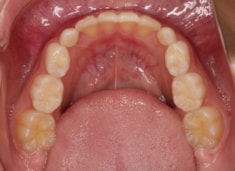

小児期ケース:反対咬合+上顎両側3番埋伏歯

(受け口+3番目の永久歯が左右両方とも埋まってしまい、はえてこない)

治療法:上顎急速拡大装置+クリアスナップ+フェイスマスク+上顎3番は開窓牽引CT写真にて位置確認

治療前